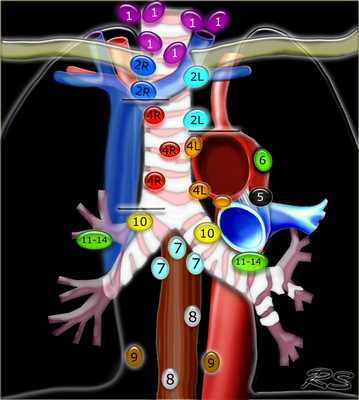

Лимфатические узлы средостения

Лимфатические узлы 3 группы не примыкают к трахее в отличии от лимфатических узлов 2 группы. Они подразделюятся на: 3А кпереди от сосудов 3Р позади пищевода/превертебрально Они не доступны при медиастиноскопии. 3Р группа может быть доступна при чреспищеводной эхокардиографии.

4R. Правые нижние паратрахеальные лимфатические узлы

- Верхняя граница: пересечение нижнего края левой плечеголовной вены с трахеей.

- Нижняя граница: нижний края непарной вены. 4R узлы распространяются до левого края трахеи.

4L. Левые нижние паратрахеальные лимфатические узлы

4L узлы расположенные слева от левой стенки трахеи, между горизонтальными линиями проведенными касательно верхней стенке дуги аорты и линией проходящей через левый главный бронх на уровне верхнего края верхнедолевого бронха. Они включают паратрахеальные узлы расположенные кнутри от артериальной связки.

Узлы 5 группы (аортопульмонального окна) расположены кнаружи от артериальной связки.

- 5. Субаортальные лимфатические узлы - Субаортальное или аортопульмональное окно расположено кнаружи от артериальной связки и проксимальнее первой ветви левой легочной артерии и лежит в пределах медиастинальной плевры.

- Парааортальные лимфатические узлы лежат кпереди и кнаружи от восходящего отдела аорты и между верхним и нижним краями дуги аорты.

![11]() 7. Подкаринальные лимфатические узлыЭти лимфатические узлы расположены ниже уровня бифуркации трахеи (карины), но не относятся к нижнедолевым бронху и артерии. Справа они располагаются каудальнее нижней стенки промежуточного бронха. Слева они располагаются каудальнее верхней стенки нижнедолевого бронха. Слева лимфатический узел 7 группы справа от пищевода. ![12]() 8. Параэзофагеальные лимфатические узлыЭти лимфатические узлы ниже подкаринальных лимфатических узлов и распространяются каудальнее до диафрагмы. На изображении слева ниже уровня карины справа от пищевода обозначен лимфатический узел 8 группы. На ПЭТ изображении слева показано накопление 18Р-дезоксиглюкозы в узле 8 группы. На соответствующем КТ изображении видно что данный лимфатический узел (голубая стрелка) не увеличен. Вероятность того что в имеется метастатическое поражение данного узла чрезвычайно высока, поскольку специфичность ПЭТ выше чем измерение размеров лимфатических узлов. ![14]() 9. лимфатические узлы легочной связкиДанные лимфатические узлы лежат в пределах легочной связки, в том числе и по ходу нижней легочной вены. Легочная связка представлена дупликатурой медиастинальной плевры охватывающей корень легкого. ![15]() 10. лимфатические узлы корня легкогоЛимфатические узлы корня расположены проксимальнее долевых узлов, но дистальнее медиастинальной дупликатуры и узлов промежуточного бронха справа. Все лимфатические узлы 10-14 групп являются N1 узлами, так как они находятся вне средостения. 1. лимфатические узлы вырезки грудины видны только на этом уровне и выше него 2. верхние паратрахеальные лимфатические узлы: ниже ключиц , справа над пересечением нижнего края левого плечеголовного ствола и трахеи, а слева над дугой аорты

3. Преваскулярные и ретротрахеальные: кпереди от сосудов (3А) и превертебральные (3Р)

4. Нижние паратрахеальные: ниже верхнего края дуги аорты до уровня главного бронха

5. Субаортальные (аортопульмональное окно): лимфатические узлы кнаружи от артериальной связки или кнаружи от аорты или левой легочной артерии.

6. Парааортальные: узлы лежащие кпереди и кнаружи от восходящего отдела аорты и дуги аорты под верхним краем дуги аорты.

7. Субкаринальные лимфатические узлы.

8. Параэзофагеальные лимфатические узлы (ниже карины).

9. Лимфатические узлы легочной связки: лежат в пределах легочной связки.